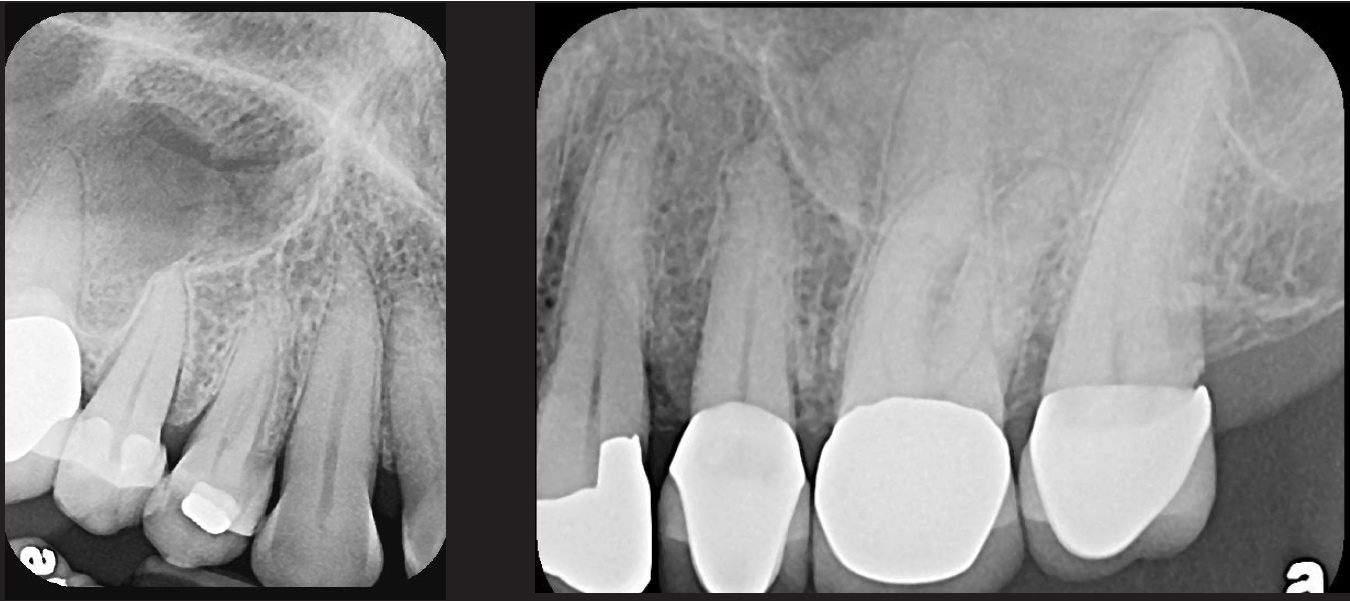

Fig 7. Presence on maxillary

anterior PSP PA radiograph of impacted canine No. 11.

Figure 7

Fig 8. PSP

PA radiograph demonstrates view of impacted supernumerary tooth

between the roots of tooth Nos. 27 and 28.

Figure 8

Fig 9. Endodontic obturation overfill visible on PA radiograph, which is

escaping the apex of tooth No. 14 and extruding into the left maxillary

sinus. A pathologic sinus congestion, in the form of a slight radiopacity

within the sinus, is noted in response to the foreign material.

Figure 9

Fig 10.

A hemostat was used to obtain this PSP PA image of a potential fixed

prosthesis abutment, tooth No. 32. The hemostat is visible in the upper

left corner of the image. Hemostat stabilization of an HW sensor is

not possible and can damage the sensor if attempted.

Figure 10

Fig 11. A PA

radiographic image showing PA pathosis associated with incomplete

endodontic obturation on tooth No. 13.

Figure 11

Fig 12. A PSP PA demonstrating

poor quality endodontic treatment on left, associated with tooth No. 31,

resulting in PA pathosis. Retreatment of root canal and replacement of

restoration on this tooth is subsequently followed periodically, as in the PA

on the right side, exposed 7 years later.

Figure 12

Fig 13. An easily placed pediatric

PSP no. 2 size right side BW radiograph shows the presence of second

molars and the normal pattern of eruption of the bicuspids in this patient,

age 7.

Figure 13

Fig 14. Bilateral BW PSP radiographs on this 8-year-old patient

demonstrate agenesis of bicuspid Nos. 20 and 29. Primary tooth Nos. K

and T must be evaluated for long-term retention.

Figure 14